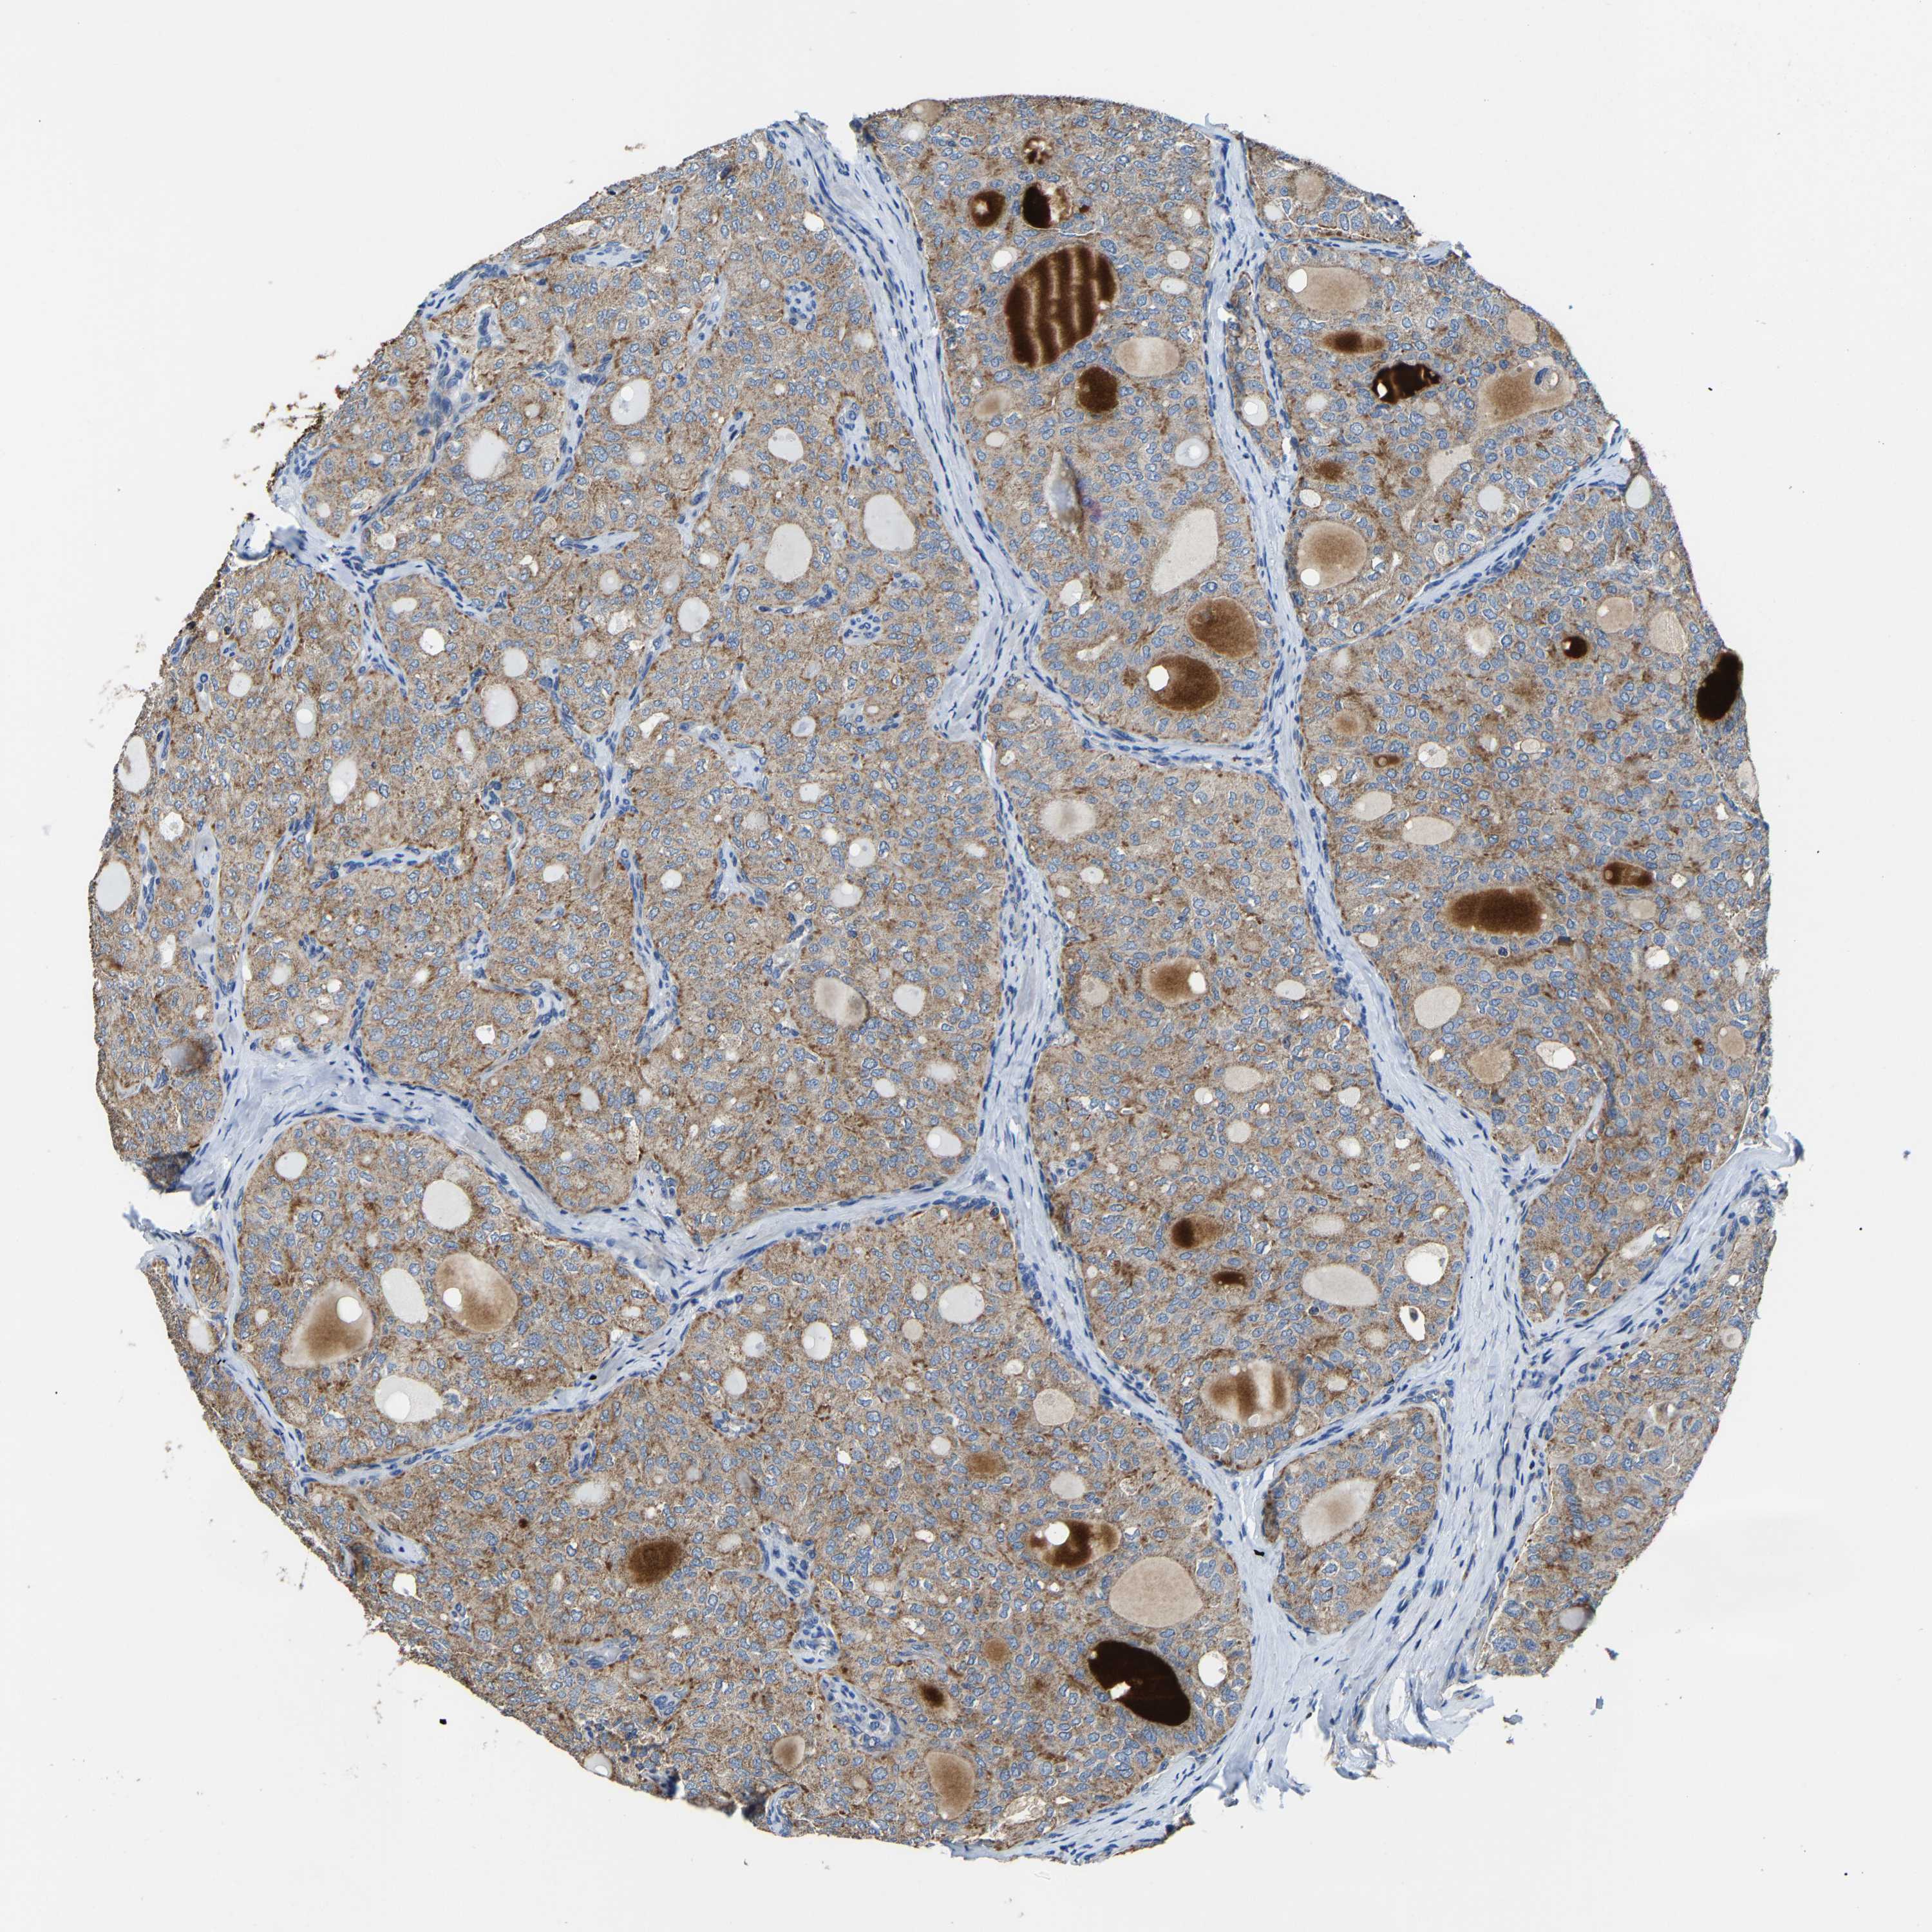

THYROID CANCER - Protein expressioni

A mouse-over function shows sample information and annotation data. Click on an image to view it in a full screen mode. Samples can be filtered based on level of antibody staining by selecting one or several of the following categories: high, medium, low and not detected. The assay and annotation is described here.

Note that samples used for immunohistochemistry by the Human Protein Atlas do not correspond to samples in the TCGA dataset.

Antibody stainingi

Antibody staining in the annotated cell types in the current human tissue is reported as not detected, low, medium, or high, based on conventional immunohistochemistry profiling in selected tissues. This score is based on the combination of the staining intensity and fraction of stained cells.

Each image is clickable and will lead to virtual microscopy that enables deeper exploration of all samples and also displays staining intensity scores, fraction scores and subcellular localization as well as patient and tissue information for each sample.

Antibody HPA020959

Antibody HPA053471

Staining

High

Medium

Low

Not detected

Intensity

Strong

Moderate

Weak

Negative

Quantity

>75%

75%-25%

<25%

None

Location

Nuclear

Cytoplasmic/membranous

Cytoplasmic/membranous,nuclear

Papillary adenocarcinoma, NOS

Follicular adenoma carcinoma, NOS